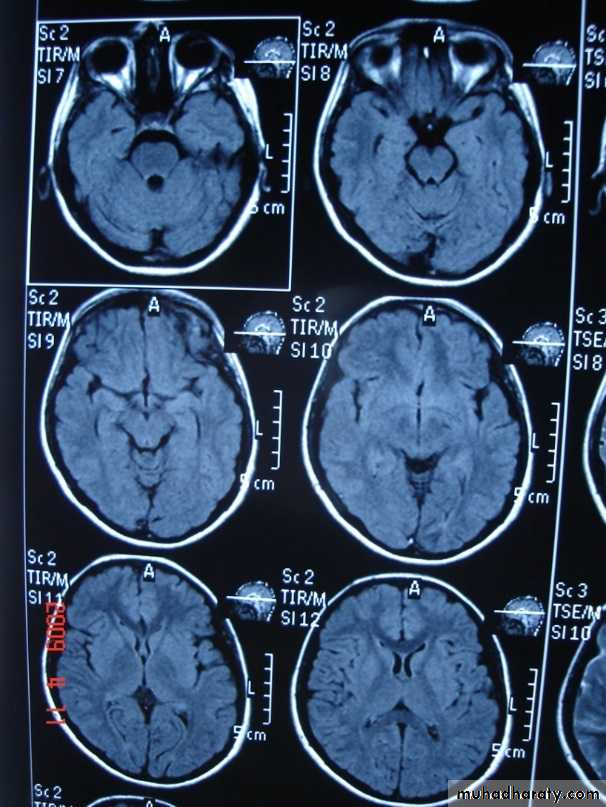

T 2/ FLAIR SEQUENCE: fluid attenuation inversion recoveryT 1w + GADOLINEUM INJECTION / SAGITAL SECTION

MRI